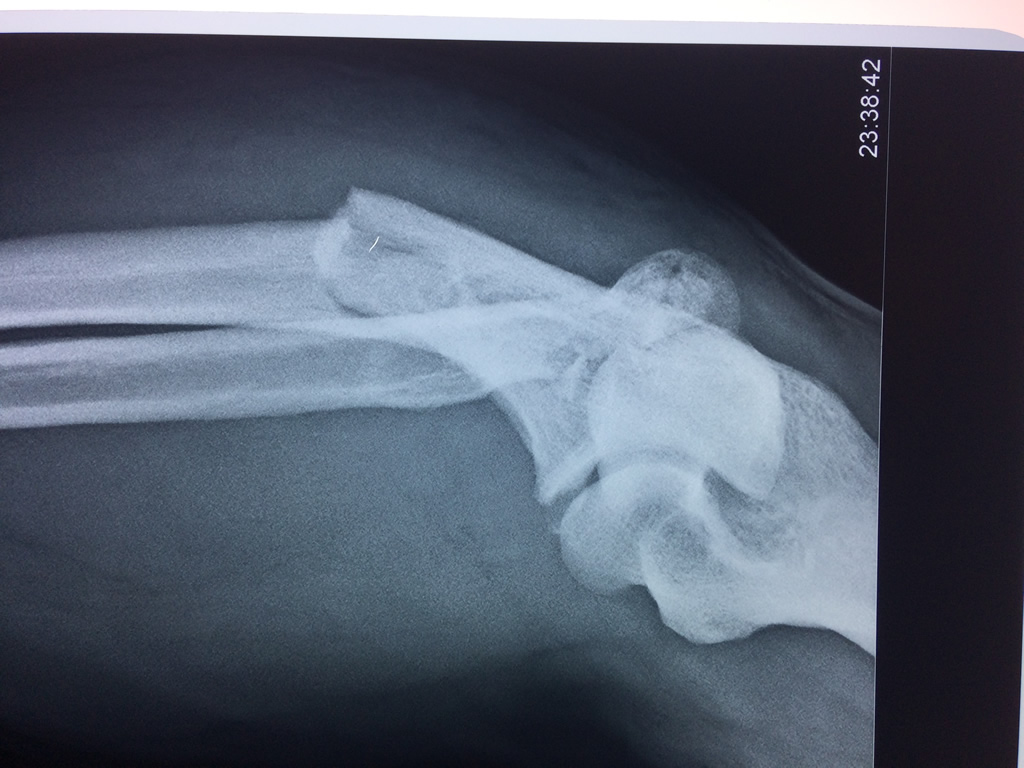

Cirugías de Calcaneo - Codo

En anatomía humana, la articulación del codo es la que une el brazo con el antebrazo, conectando la parte distal del hueso húmero con los extremos proximales de los huesos cúbito y radio.

La articulación principal que constituye el codo se denomina humero radio-cubital y puede dividirse en dos partes bien diferenciadas, la articulación humero-radial y la humero-cubital.

Por otra parte el cúbito y el radio forman también una articulación entre si en las proximidades del codo, la cual se denomina articulación radio-cubital proximal.